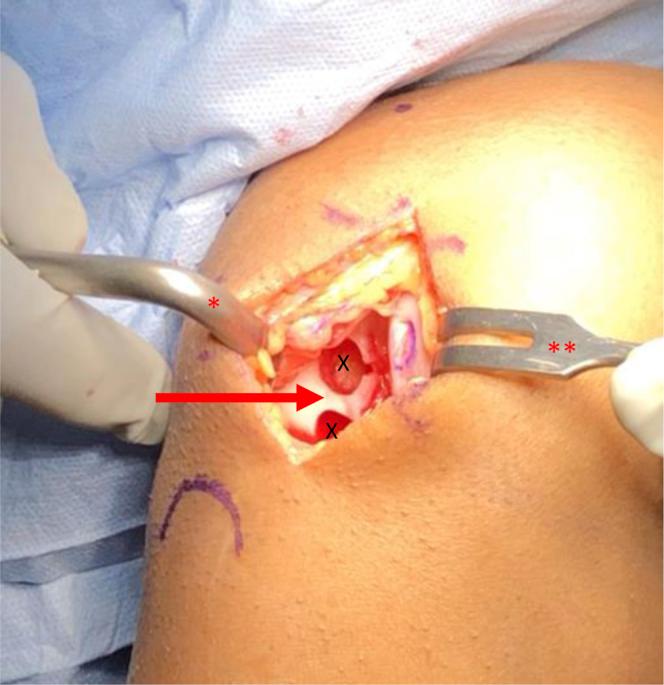

使用预切割骨软骨异体移植塞和微粉化细胞外软骨增强技术进行供区回填的膝关节局灶性软骨损伤自体骨软骨移植术

Osteochondral Autograft Transfer for Focal Cartilage Lesions of the Knee With Donor-Site Back-Fill Using Precut Osteochondral Allograft Plugs and Micronized Extracellular Cartilage Augmentation.

Osteochondral autograft transfer (OAT) allows for the treatment of focal chondral lesions of the femoral condyles. Patients undergoing OAT have been shown to have the greatest rate and quickest return to sport of any cartilage-restoration procedure. Disadvantages encountered with the OAT procedure include limited donor sources, small treatable lesion size, and donor-site morbidity. Here, we describe our preferred technique of open OAT with donor-site back-filling using precut fresh osteochondral allograft plugs and micronized extracellular cartilage augmentation. Advantages to this technique include single-stage transfer of living autologous osteochondral grafts allowing for early ambulation, predictable return to sport, enhanced long-term graft survival, and decreased donor-site morbidity secondary to fresh osteochondral allograft back-fill.

自体骨软骨移植(OAT)可用于治疗股骨髁的局灶性软骨损伤。接受OAT治疗的患者在所有软骨修复手术中恢复运动的比例最高且恢复速度最快。OAT手术存在的缺点包括供体来源有限、可治疗的损伤面积小以及供体部位的并发症。在此,我们描述了一种开放式OAT的首选技术,即使用预先切割的新鲜骨软骨同种异体移植栓进行供体部位回填以及微粉化细胞外软骨增强。该技术的优点包括单阶段移植活的自体骨软骨移植物,允许早期下床活动、可预测的运动恢复、提高移植物长期存活率,以及因新鲜骨软骨同种异体移植回填而降低供体部位并发症。